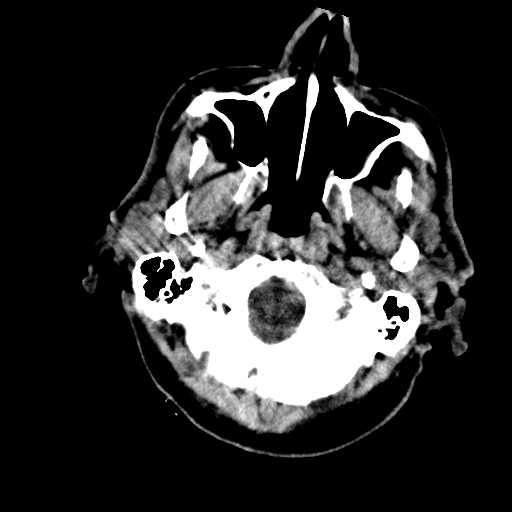

Figure 1: Illustrative examples of different types of brain hemorrhages in CT scans. The hemorrhagic regions are highlighted in red. (a) IPH, (b) IVH, (c) EDH, (d) SAH, (e) SDH.

The dataset used in this study was collected from two medical centers in Tehran, Iran: Rasoul Akram Hospital and Firouzabadi Hospital, over a period spanning 2018 to 2024. All CT scans were manually labeled hierarchically by two board-certified neurosurgeons to ensure accurate classification of ICH subtypes. The labeling process involved an initial annotation by one neurosurgeon, followed by validation and verification by a second expert to minimize errors and inconsistencies. Fig. 1 illustrates representative examples of different ICH subtypes in brain CT scans. The hemorrhagic regions are highlighted in red for better visualization. These annotated examples provide insight into the distinct imaging characteristics of each hemorrhage type, emphasizing the variability in their locations and appearances within the brain. The study received ethical approval, and data collection was conducted in compliance with institutional review board (IRB) regulations and the Declaration of Helsinki, ensuring patient confidentiality and adherence to ethical standards.